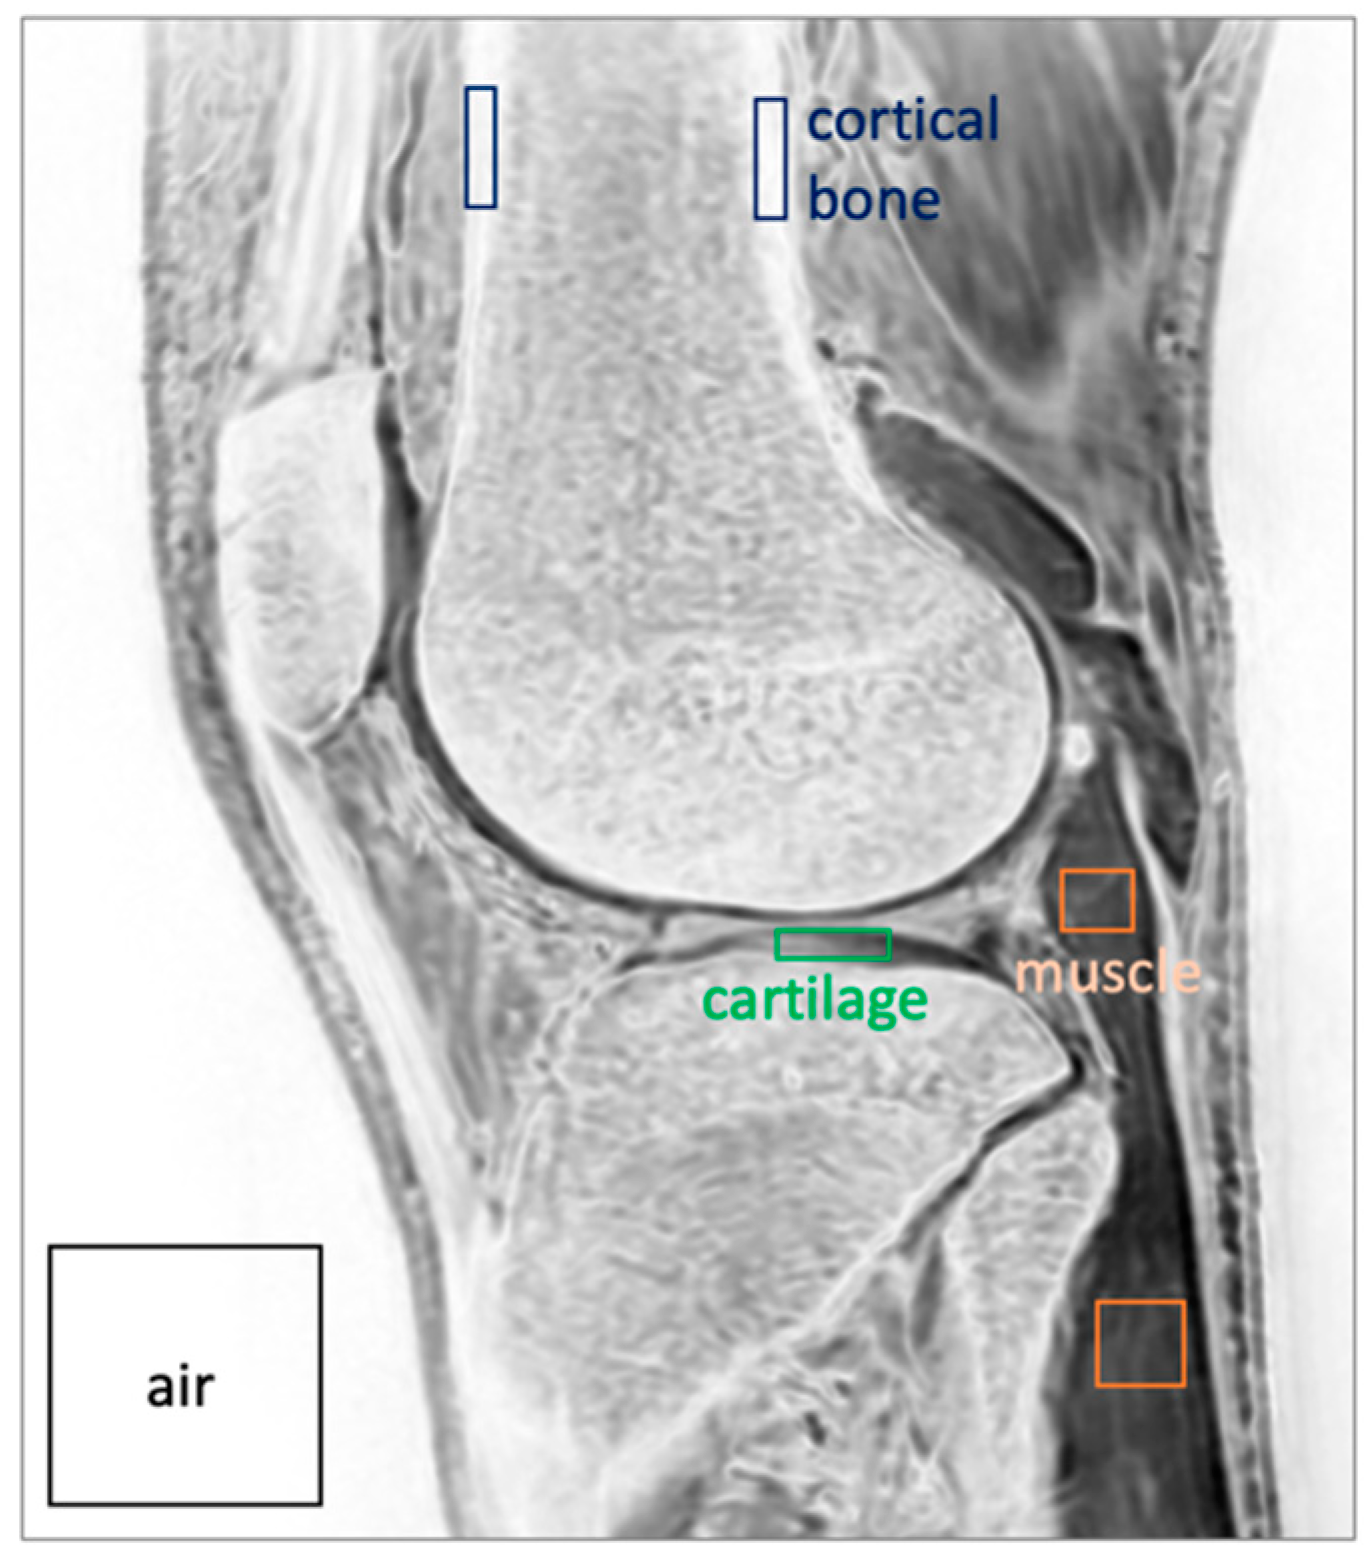

| Measurement | δUTE processed | FE processed | FE HR-DLR processed | p-value |

| Bone SNR | 104 (19.3) | 304 (271) | 410 (179) | 0.086 |

| Muscle SNR | 63.1 (22.2) | 116 (70.0) | 168 (64.4) | 0.716 |

| Cartilage SNR | 69.8 (23.5) | 166 (141) | 233 (96.1) | 0.067 |

| Bone-Muscle CNR | 40.5 (8.4) | 187 (205) | 242 (139) | 0.137 |

| Bone-Cart CNR | 33.8 (6.6) | 138 (148) | 177 (103) | 0.124 |